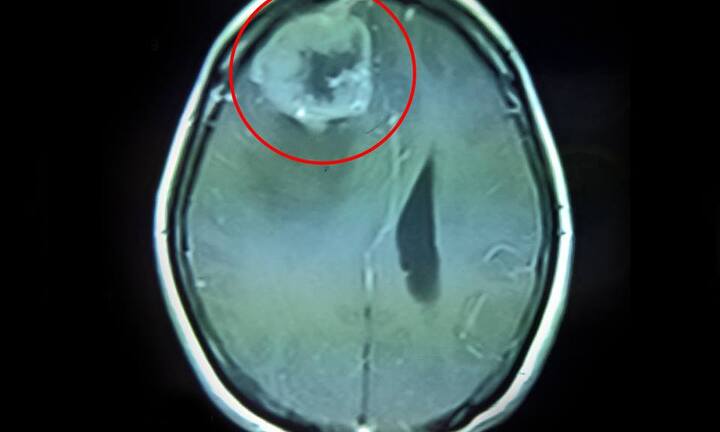

Tình trạng nghiêm trọng của nữ sinh 15 tuổi. Ảnh: Công lý |